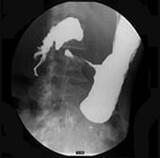

问题 女,56岁,上腹部钝痛、腹胀不适1月余,纳差、消瘦,影像检查如图,最可能的诊断是 ( )

选项 A.胃幽门管溃疡 B.胃腺癌并幽门狭窄 C.胃淋巴瘤 D.胃间质瘤 E.胃恶性间质瘤

答案 B